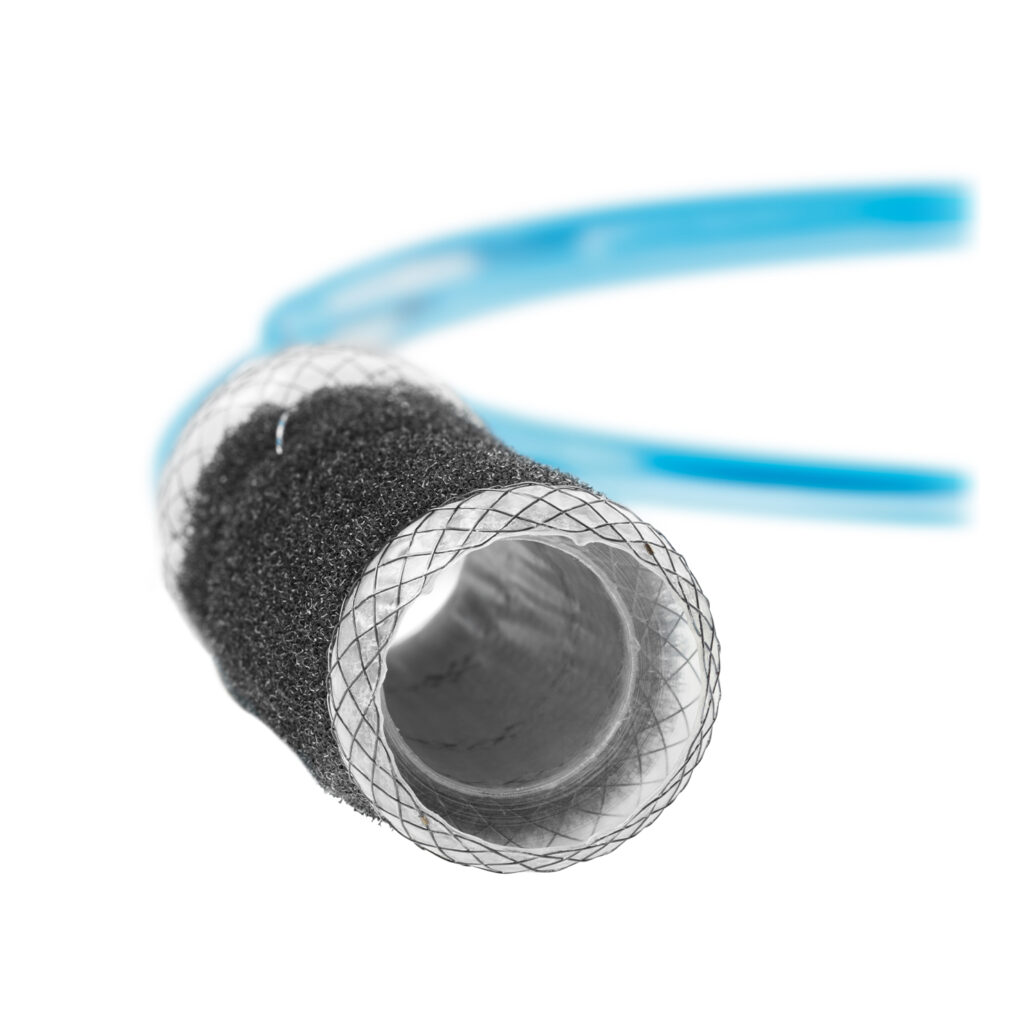

The VacStent GI™ combines two reliable methods for the treatment of leakage and anastomotic insufficiency: while the fully encased stent completely covers the defects, the wound cavity is drained by continuous suction.

- Continuous drainage

- Reliable vacuum

- Covers the wound cavity

- Promotes granulation